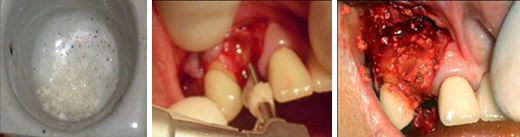

雷射植牙~龍霖醫師

Procedure: Block Bone Graft &Implantation, (Staged Approach)

Xenograft –Bio-Oss

14wks after i1

Subepithelial C.T. graft

Pre-treatment                                                Post-treatment

2010-05-25